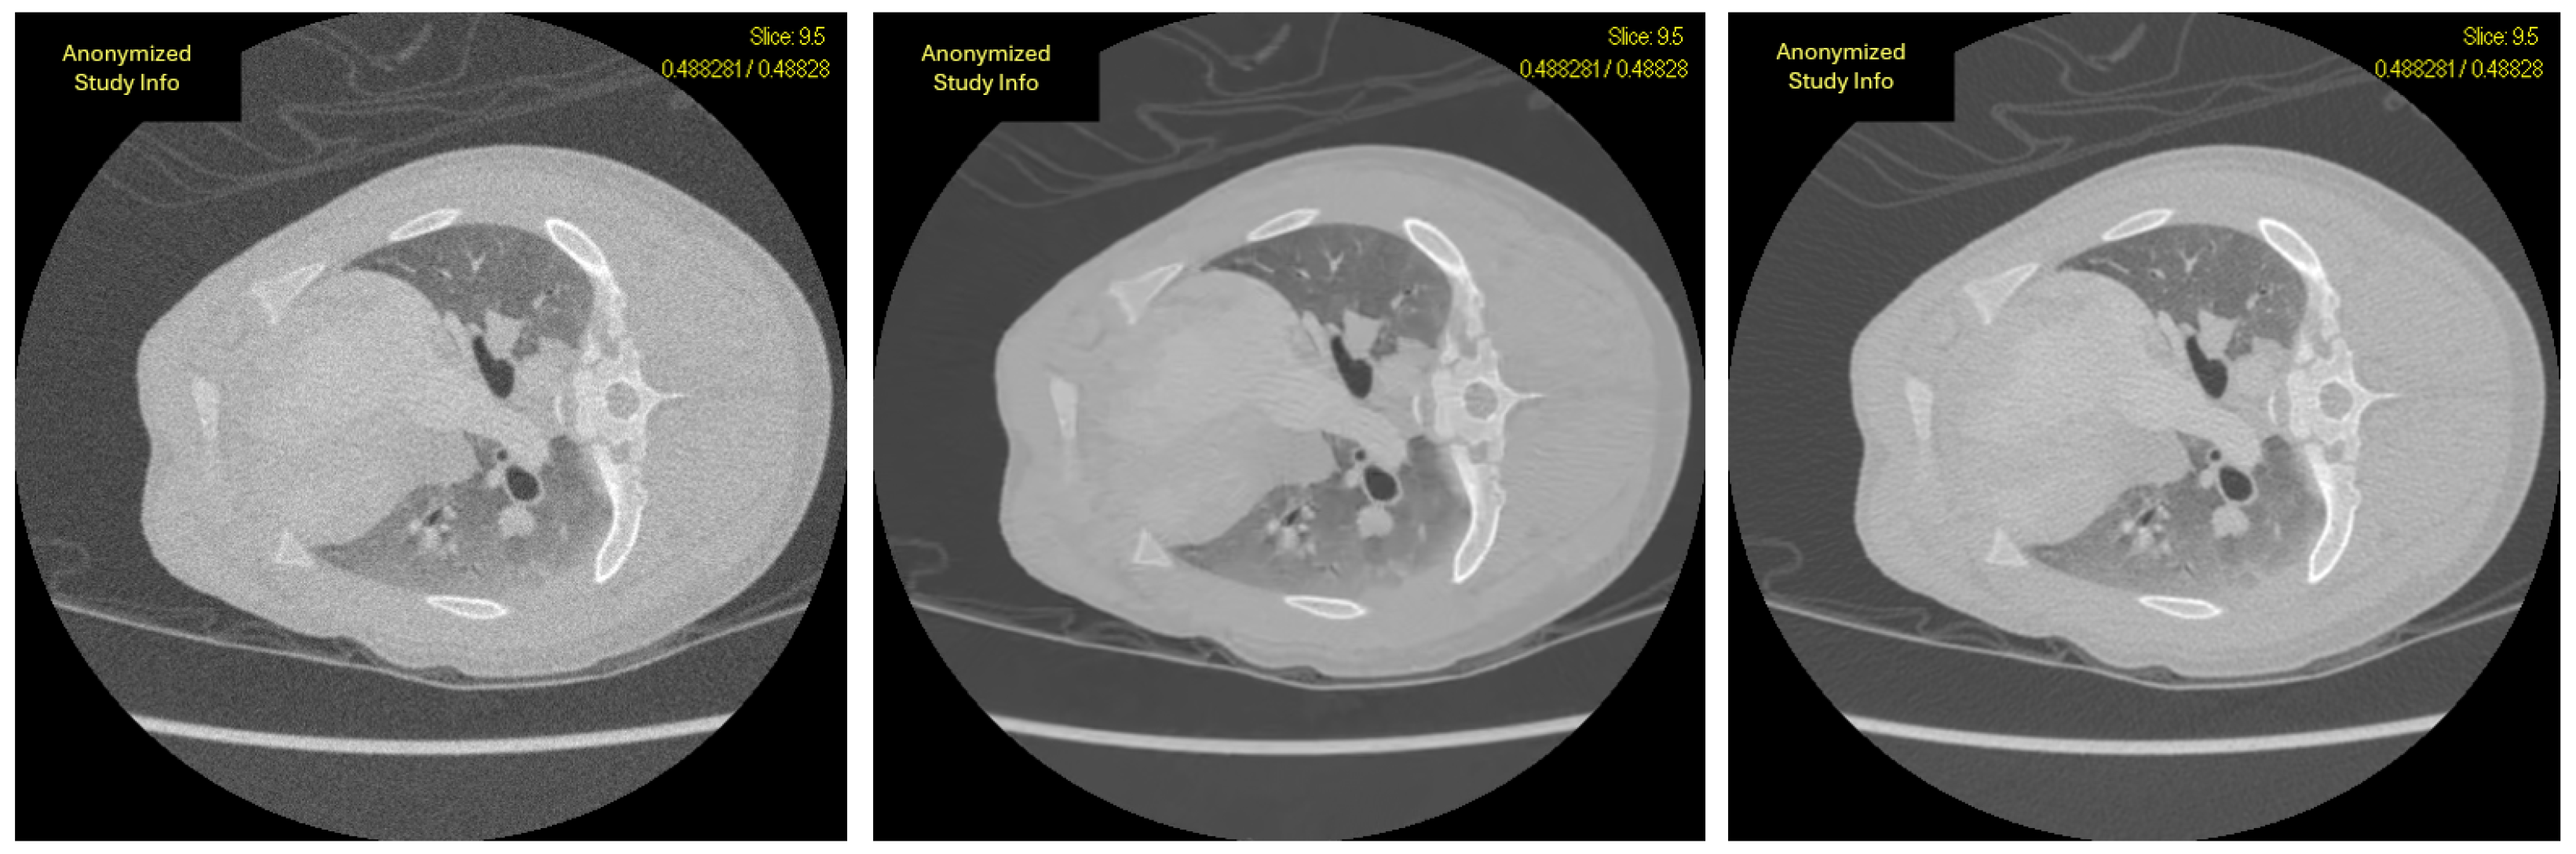

The myocardial and pulmonary regions from Figure 2 were magnified and are presented in Figure 3. A comparative inspection of the three images clearly demonstrates that the noise present in the 20 mA acquisition (middle) is substantially reduced in the reconstructed 80 mA image (right). The myocardial structures appear well preserved, while the pulmonary vessels are more distinctly delineated, indicating effective noise suppression and structural recovery achieved by the proposed reconstruction method. This is comparable with the original 80 mA scan (right).

Figure 3. Comparison of image quality across different dose levels and reconstruction when zoomed. The 20 mA image (left) shows degradation from the low-dose simulation; the reconstructed 80 mA image (middle) demonstrates the recovery achieved by the proposed noise correction model; and the 80 mA image (right) serves as the high-quality reference. The window level and window width used in this example are −875 and 4298, respectively, representing a full dynamic view in this case.